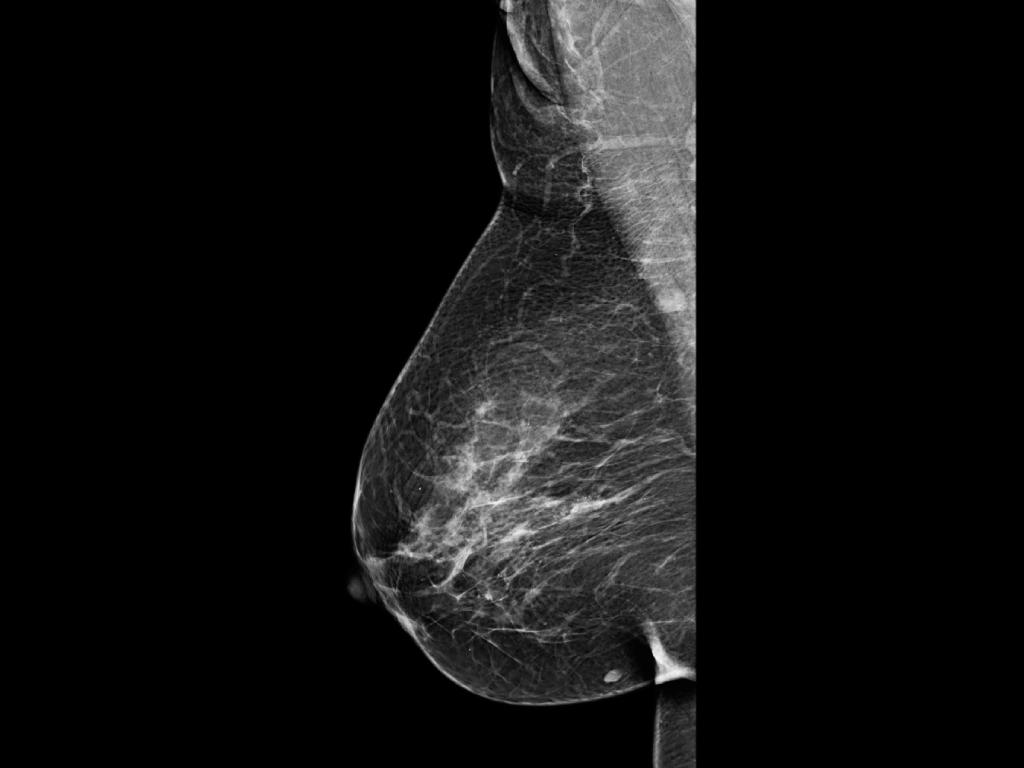

O mês de outubro há muitos anos tem sido usado no mundo todo como o período de maior conscientização para o câncer de mama. É importante entender melhor os sintomas e as diversas formas de detecção, que variam para cada paciente. Os exames de diagnóstico como ressonância magnética, uso do ultrassom de mamas e a mamografia tem sido um dos grandes diferenciais no diagnóstico precoce e na melhor escolha do tratamento a ser adotado.

Mito 3: "A mamografia é dolorosa e perigosa."

Realidade: Esta é uma crença popular associada à compressão da mama, que pode causar algum desconforto. No entanto, esse processo é fundamental para obter uma boa imagem interna e permitir um diagnóstico preciso. Na realidade, os níveis de dor são geralmente mínimos e não representam risco algum para a paciente.